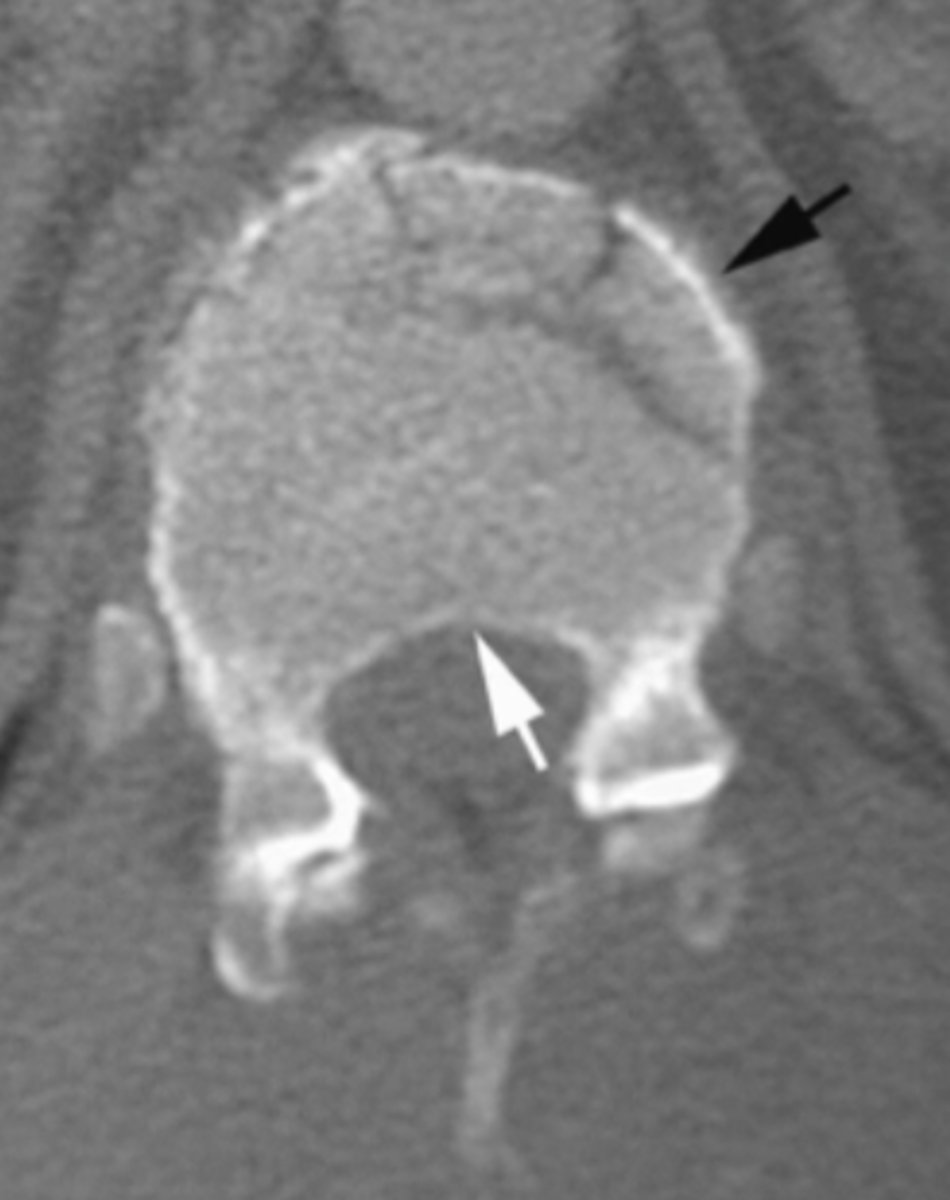

Spondylolysis

What is the issue?

ankylosing spondylitis